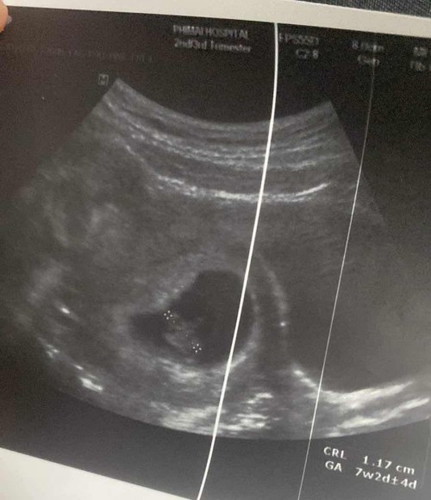

ตรวจรอบแรก8สัปดายังไม่เห็นหัวใจล่าสุด10สัปดายังไม่เห็นกังวลมากค่ะหมอนัดตรวจอีกทีอาทิตย์หน้า อันนี้ภาพตอน8สัปดา